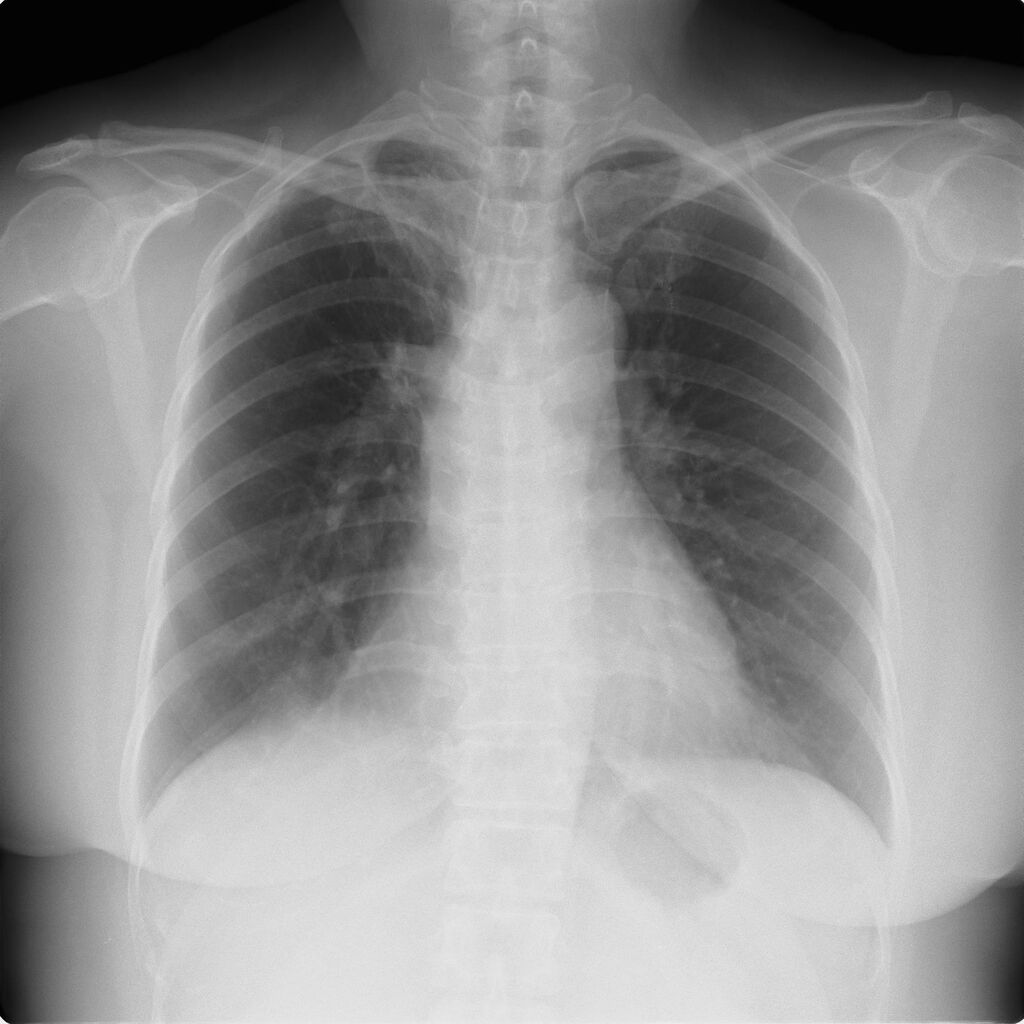

外来でよくみられる肺炎、マイコ・クラミジア・肺炎球菌・ウイルス(RSウイルス・hMPV・インフルエンザウイルスA・B)について実際に経験、外来で治癒した症例を提示します。軽症な変化のものが大多数ですが中には重症なものも紛れていて、注意が必要になります。

【マイコプラズマ肺炎】